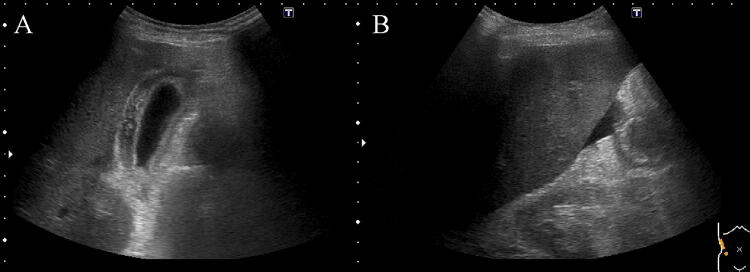

Fig. 2.

An US examination revealed thickening of the gallbladder wall (a) and ascites (b)

An 87-year-old man was admitted to our hospital for anorexia for several days, high-grade fever from the previous day, and liver dysfunction. Of note, he had a history of hypertension, diabetes mellitus (DM), and angina. Physical examination findings included: clear consciousness; height, 163 cm; weight, 48 kg; blood pressure, 66/40 mmHg; heart rate, 75/min; respiratory rate, 22/min; oxygen saturation of peripheral artery, 96%; and body temperature, 38.1 °C. He had no surface lymphadenopathy. Laboratory findings included: white blood cell (WBC) count, 4.2 × 109/L; hemoglobin, 9.6 g/dL; platelet count, 106 × 109/L; lactate dehydrogenase (LDH), 1662 IU/L; aspartate aminotransferase (AST), 6562 IU/L; alanine aminotransferase (ALT), 1407 IU/L; alkaline phosphatase (ALP), 509 IU/L; γ-glutamyl transpeptidase (γ-GTP), 130 IU/L; total bilirubin, 2.7 mg/dL; prothrombin time (PT), 20.3 s; international normalized ratio (INR), 1.73; blood urea nitrogen (BUN), 34.4 mg/dL; and creatinine, 1.4 mg/dL. Serologic tests were all negative for hepatitis A, B, C, and E. Computed tomography (CT) performed at admission revealed no distinct nodules or masses in the liver, but mild splenomegaly, multiple hypodense splenic lesions, and para-aortic lymph node swelling (Fig. 1a–c). Antibiotics were administered intravenously for suspected acute cholangitis and sepsis, but the fever persisted. Abdominal ultrasonography (US) and magnetic resonance imaging (MRI) performed 2 days later newly depicted gallbladder wall thickening and ascites (Figs. 2, 3). On the same night, the patient presented with grade II hepatic encephalopathy, with blood tests showing a decrease in platelet count and worsening liver function suggestive of “acute type” ALF with hepatic coma and disseminated intravascular coagulation (DIC). While consideration was being given to treating acute liver failure, the patient suddenly developed ventricular fibrillation and died despite immediate resuscitation measures on day 3 of hospitalization.